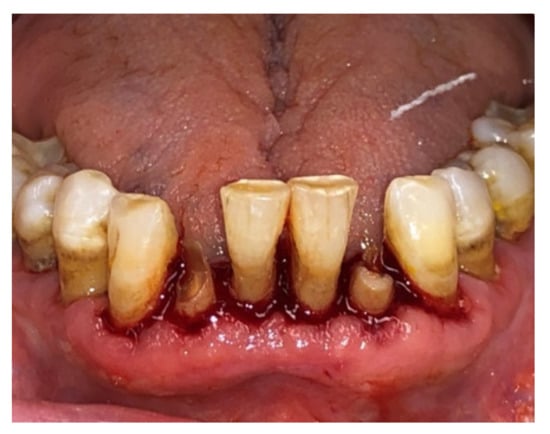

| Tissue colour: | 50% of gingiva red |

| Granulation tissue: | Present | |

| Incision margin: | Not epithelialized, with loss of epithelium beyond incision margin | |

| Suppuration: | Present | |

| Incision margin: | Not epithelialized, with connective tissue exposed | |

| Suppuration: | None | |